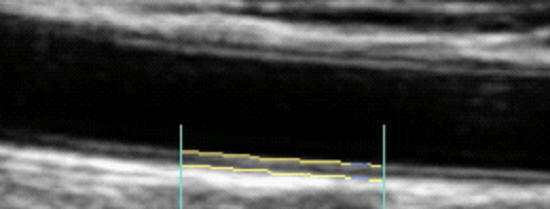

Carotid Artery Intima-Media Thickness (brackets, above), the combined thickness of the endothelial and muscular layers of the Common Carotid Artery, reflects your current propensity to form plaque and risk of future atherosclerotic events (heat attack, stroke, etc.). IMT increases with age, on average at 0.01 mm/year, and IMT rate of change relates to risk factor control efficacy. Slow progression or stabilization of IMT reflects good risk factor control. Conversely, rapid IMT progression indicates that we have more work to do. All phenomena shown to increased CV risk will increase IMT while effective therapeutic efforts will attenuate IMT (discussed in detail elsewhere on this website).

While IMT is systemic, atherosclerotic plaque is focal, and above we see mild plaque at the level of the carotid bulb. Change in arterial physiology (risk factor control) determines IMT, which in turn determines rate of plaque progression and overall atherosclerotic risk.

Three studies have looked at the effect of Nattokinase (at different doses) on IMT and Common Carotid Artery plaque progression. While carotid plaque is not coronary plaque, directional change in carotid plaque will correlate with plaque progression/regression elsewhere within one's vasculature.